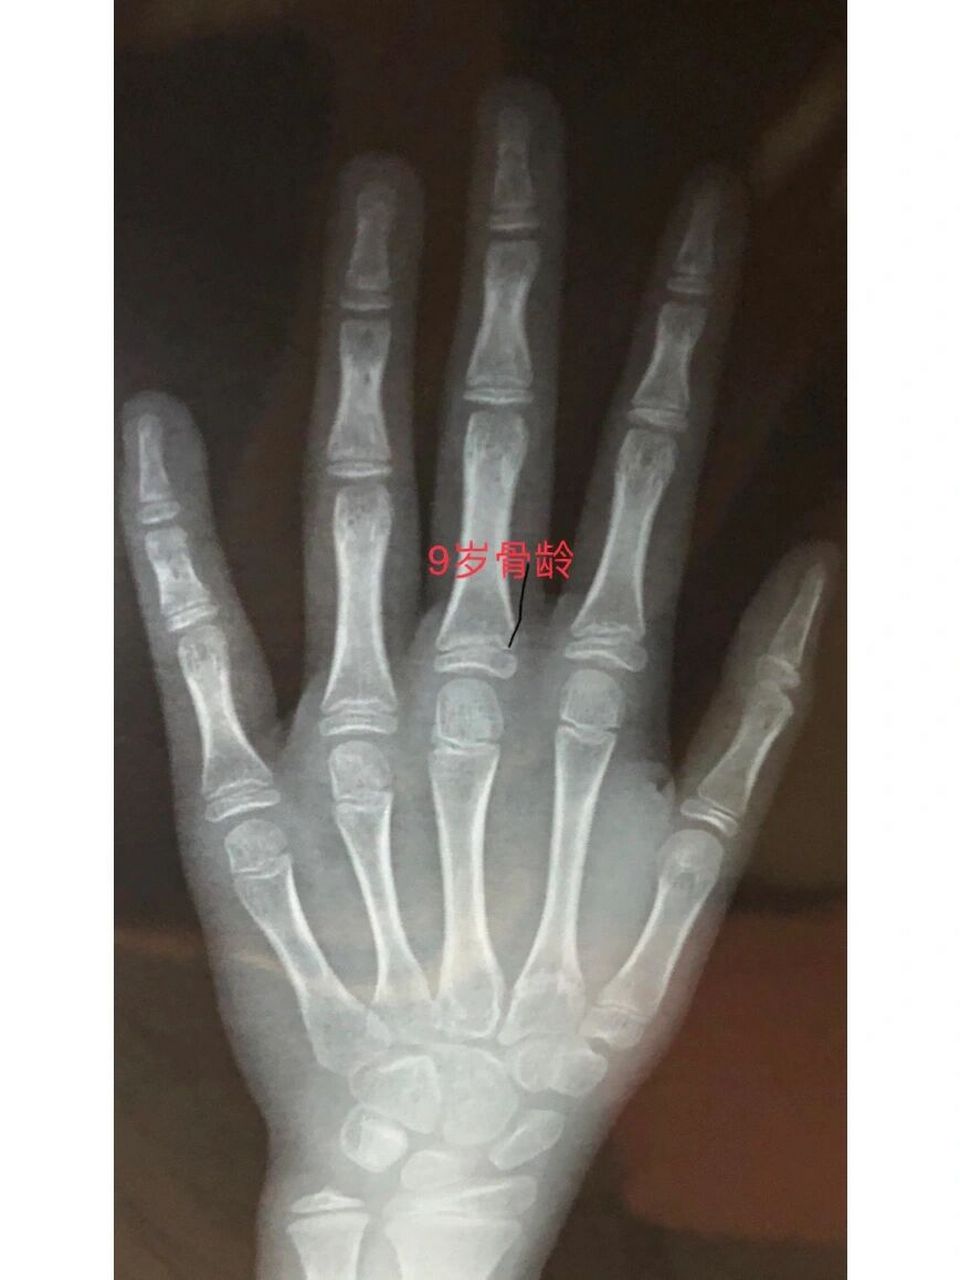

这个骨龄有多少?

图片尺寸720x4024